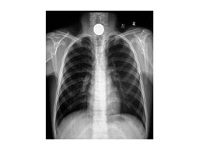

小儿脓胸